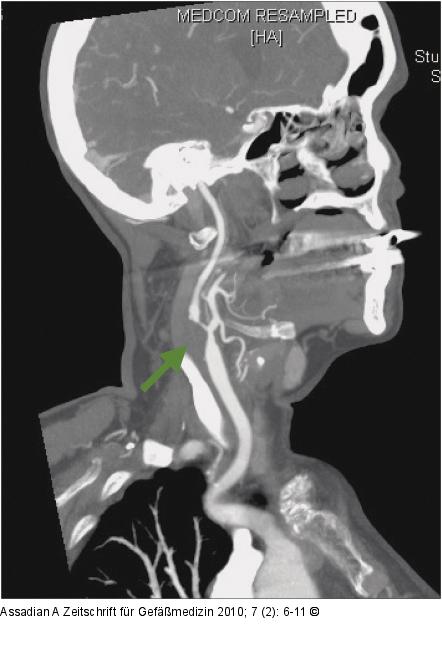

Abbildung 6: CT-Angiographie CT-Angiographie der rechten Karotis bei Zustand nach Thrombendarterektomie und Patchverschluss vor 14 Jahren und asymptomatischer Restenose (grüner Pfeil). |

CT-Angiographie der rechten Karotis bei Zustand nach Thrombendarterektomie und Patchverschluss vor 14 Jahren und asymptomatischer Restenose (grüner Pfeil). |